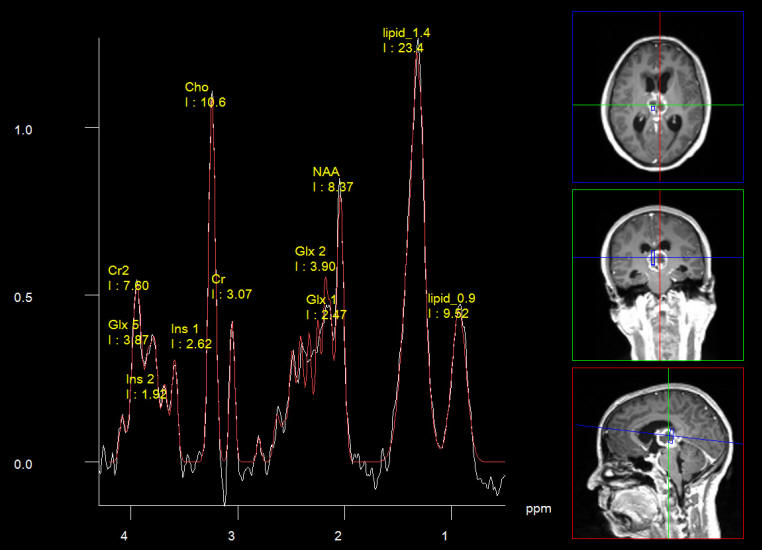

Short Echo spectroscopy in favor of pinealoblastoma.

Spectroscopy short TE showing low choline ratio? with high lipids 1.3 and 0.9.